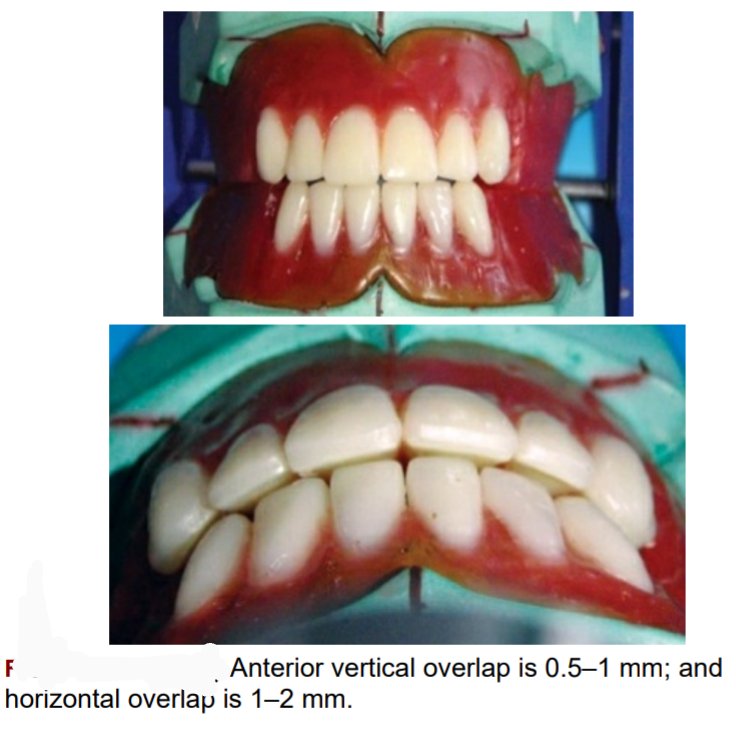

🛑The vertical overlap (over bite) between the maxillary and mandibular

incisal edge should be 0.5–1 mm, and the horizontal overlap (over jet) between

the maxillary and mandibular incisal edges should be 1–2 mm.

🛑The horizontal overlap should be uniform from left maxillary to right maxillary canine